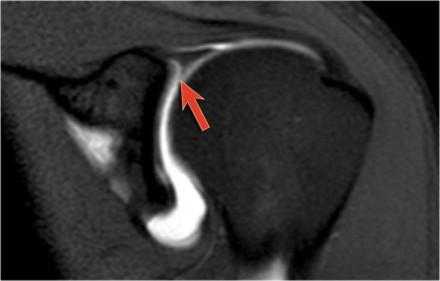

Обратите внимание на красную стрелку указывающую на небольшое повреждение Пертеса, которо не визуализировалось при стандартной аксиальной ориентации.

На аксиальном МРТ изображении показана акромиальная кость с дегенеративными изменениями, такими как субхондральные кисты и остеофиты (стрелка).